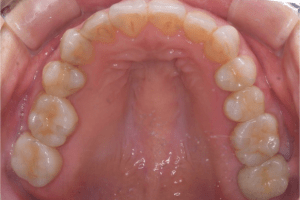

治療前:上の歯

担当医師所見:

臼歯部に残根状態の歯牙があり、またカリエス(虫歯)の散在が認められる。残根部分の両隣在歯は欠損部に対して傾斜し始めている。

治療後:上の歯

左上第1大臼歯は抜歯し、仮歯に置き換えた後治癒を待ちジルコニアBrで補綴。また右上第1大臼歯は根管治療終了後にジルコニアクラウンで補綴。前歯部は審美性を考慮しジルコニアボンドにて補綴した。 色調、形態共に調和がとれている。